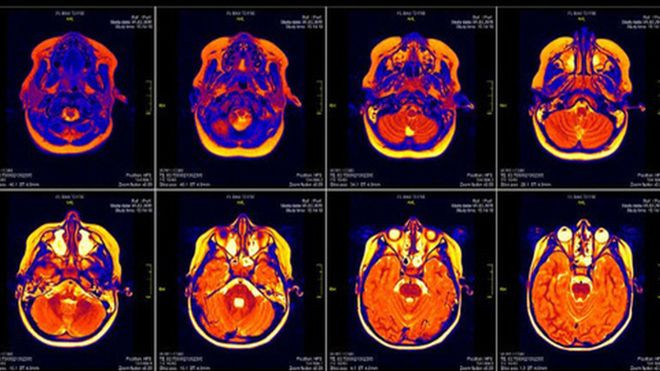

Hình ảnh não bộ qua máy quét cộng hưởng từ MRI.